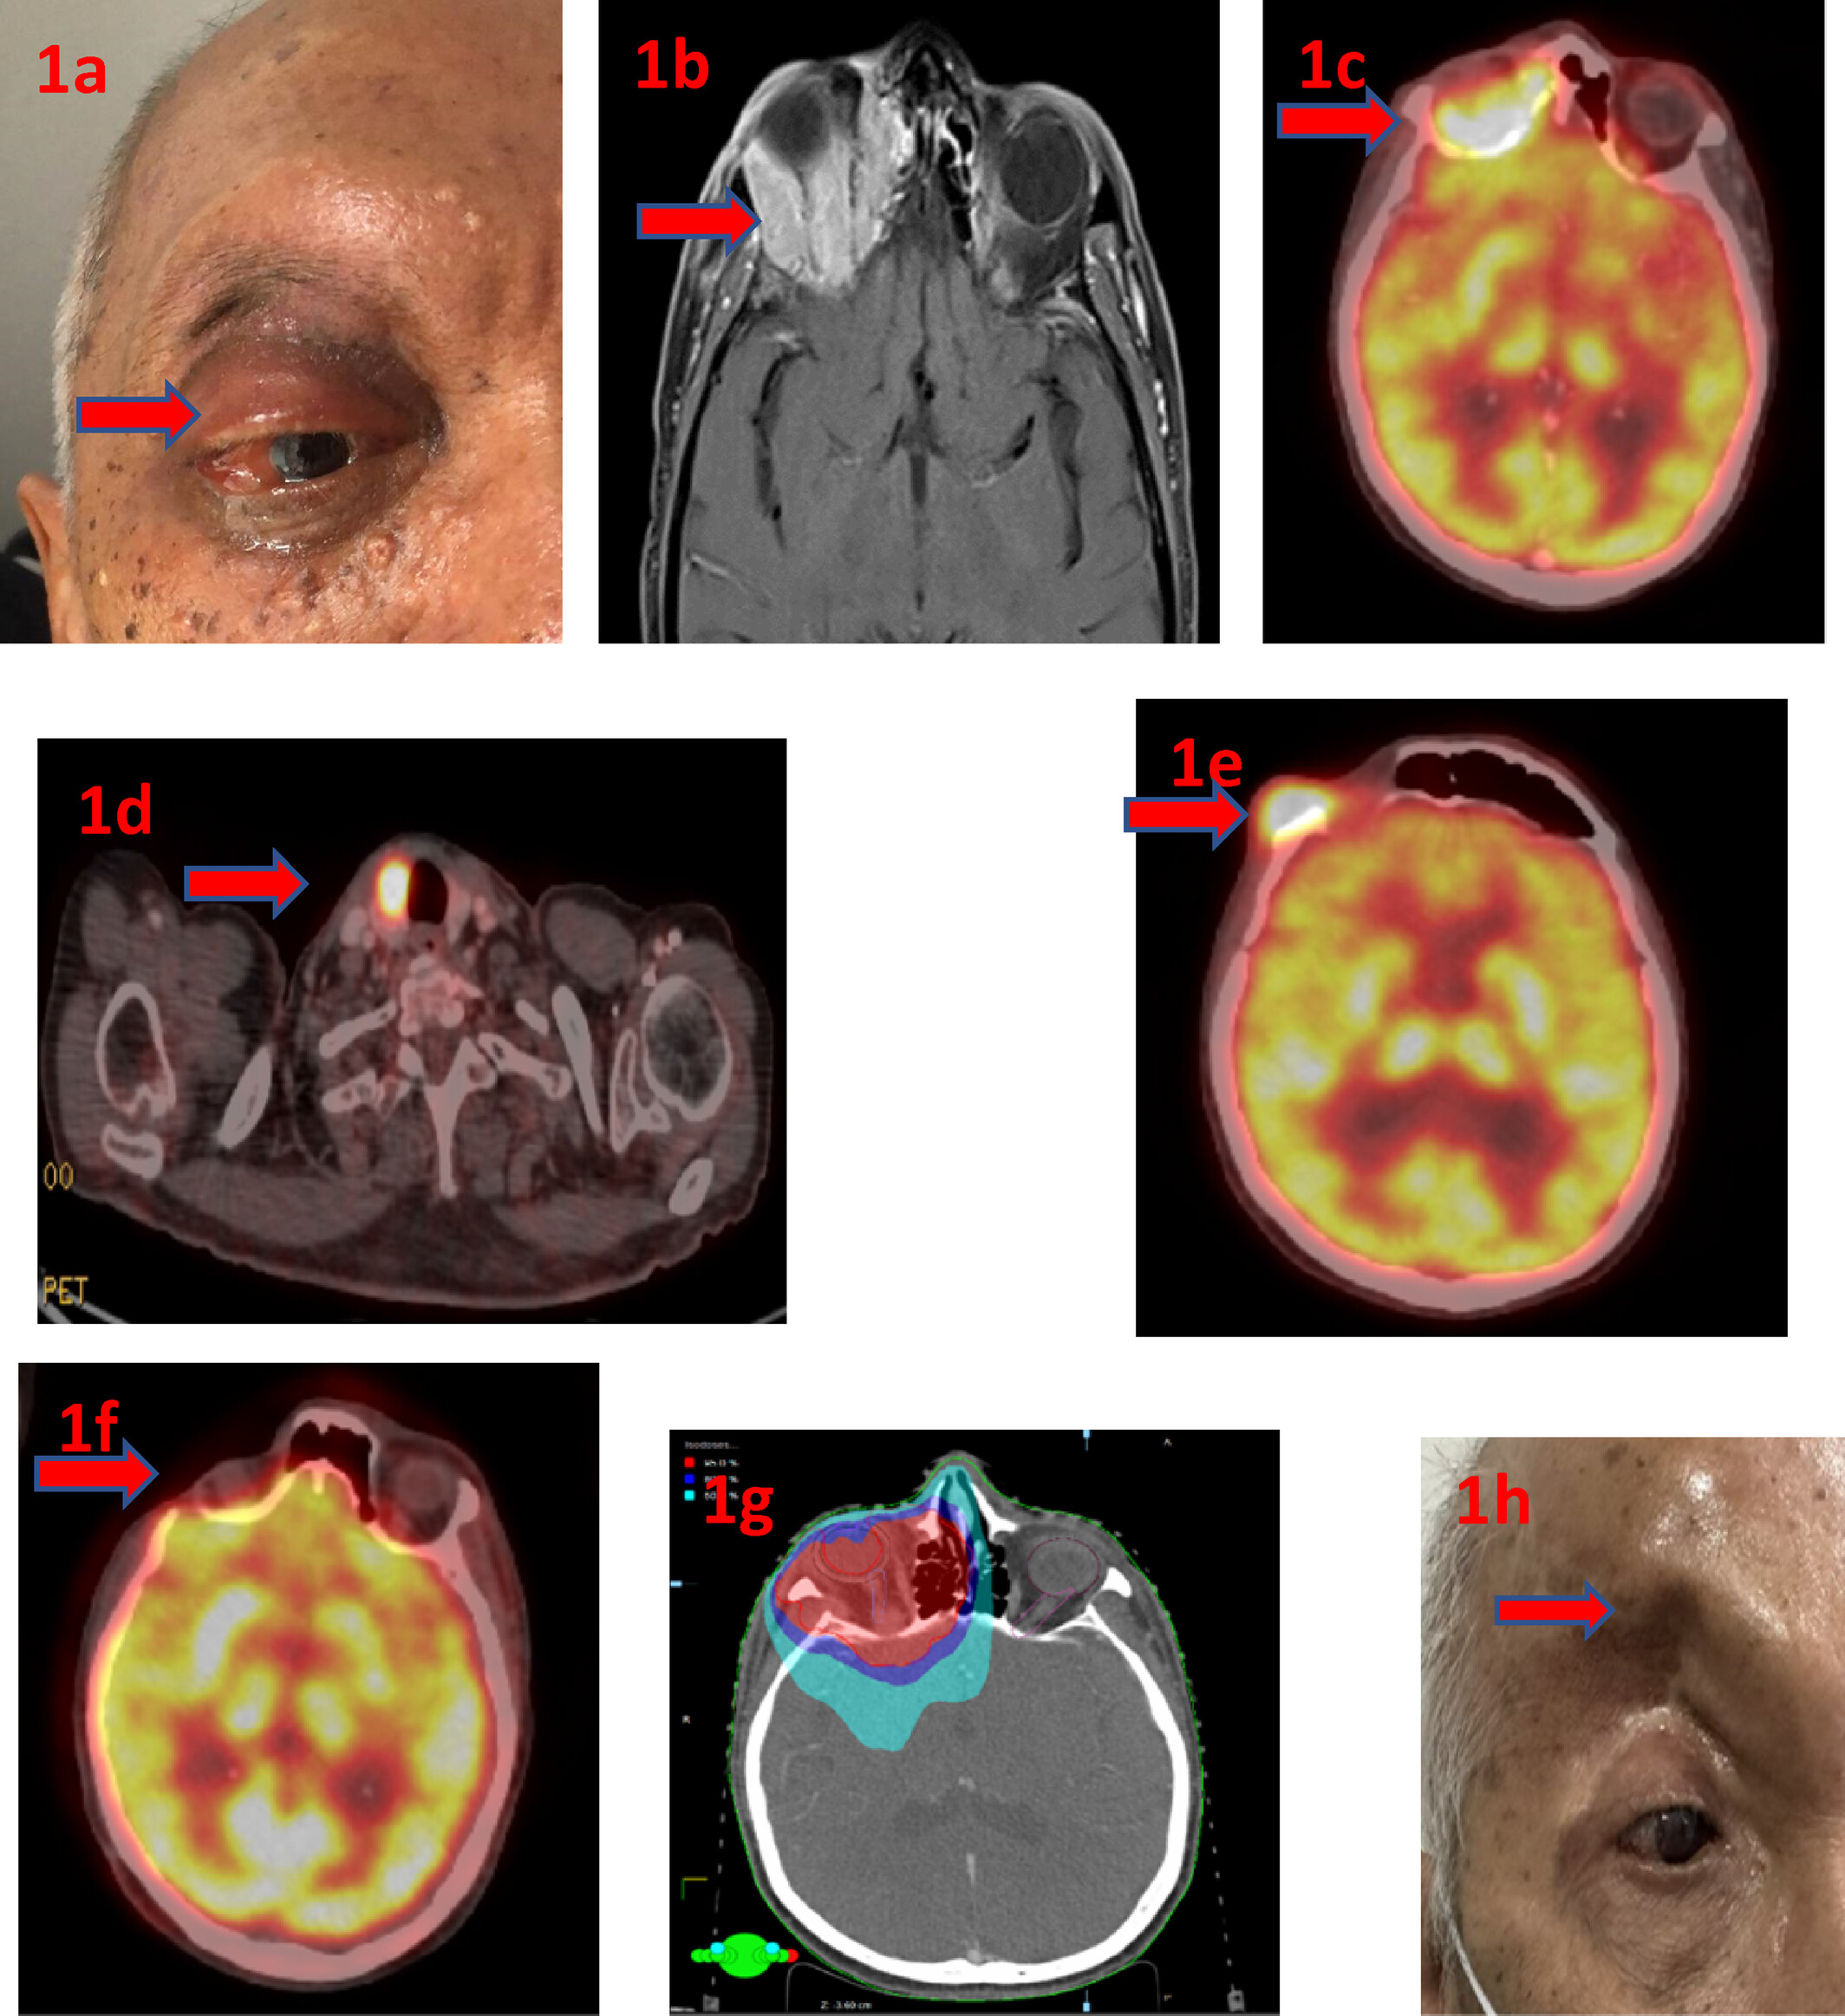

Case Report: Primary Squamous Cell Carcinoma of the Orbit in a Patient With Carney's Syndrome Treated With Multidisciplinary Approaches

Squamous cell carcinoma (SCC) is a rare malignancy of invasive epithelium with keratinocyte differentiation, and it is the most common form of eyelid malignant neoplasm, comprising 5%–10% of malignancies. While …

A 62-year-old South Asian male presented with a painful swelling in the lateral aspect of the right eyebrow and protrusion of the eyeball in August …